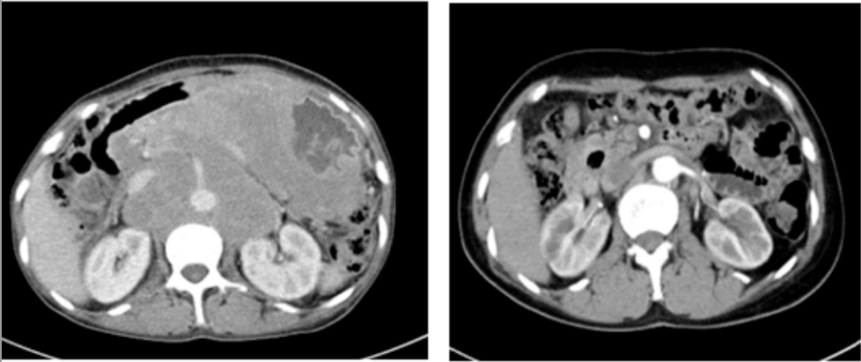

两年前,张阿姨(化名)的生活被一场突如其来的疾病打乱。持续地恶心、呕吐,整整一个月几乎未进食。在家人的陪伴下,来到国文医院进行全面检查。胃镜结果和腹部CT带来了一个沉重的消息:胃部弥漫大B细胞淋巴瘤,并且已形成一个直径约10厘米的巨大包块。这不仅仅是一个肿瘤,更是一枚“不定时炸弹”。因为淋巴瘤的侵犯,张阿姨的胃壁已经形成了巨大溃疡,随时可能引发消化道大出血或穿孔,性命危在旦夕。

历经八个周期的规范化疗,最终的评估结果让所有人欢欣鼓舞:张阿姨的病情在影像学检查上显示肿瘤已消失。